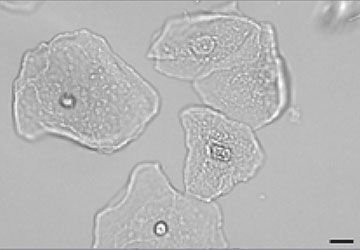

What do you see in this image?

Squamous — Epithelial cell